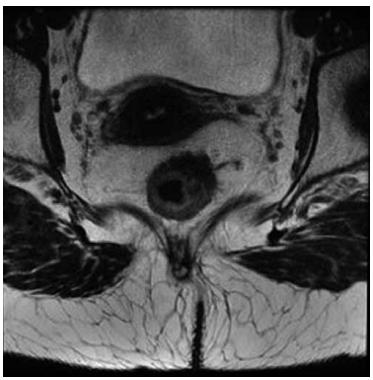

A ressonância magnética de pelve do paciente caracteriza estadiamento clínico T3bN0:

(Arquivo pessoal; imagem utilizada com autorização)

A ressonância magnética de pelve do paciente caracteriza estadiamento clínico T3bN0:

(Arquivo pessoal; imagem utilizada com autorização)